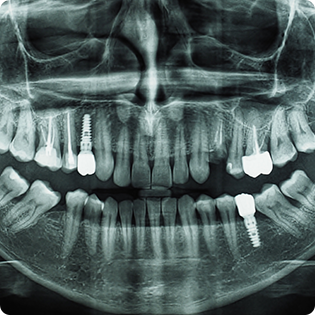

Kada se ugradi zubni implant, kost ne samo da se više ne povlači, već raste oko implanta, tako da implant postaje deo organizma. Današnji implanti su bioaktivni, što znači da pospešuju rast kosti, kao što nedostak korena ili implanta pospešuje gubitak kosti.

Ugradnja implanta na mestu nedostajućih omogućava da ostali zubi ostanu na svojim mestima, što je veoma važno, jer svaki zub tačno naleže na zub u suprotnoj vilici. Ako se posle gubitka zuba ne ugradi implant, okolni zubi se pomeraju i nastaje nepravilan zagrižaj.

Ako se implant ugradi u prvih nekoliko meseci, susedni zubi će ostati na svom mestu i krunica će savršeno popuniti prazninu. Ako se sačeka oko godinu dana, može doći do blagog pomeranja zuba ili povlačenja kosti, pa je potrebna dodatna priprema pre ugradnje, i krunica se prilagođava novonastaloj situaciji. Ako se čeka više godina, implant i dalje jeste opcija, ali se postupak značajno komplikuje, jer se kost povukla i zubi su zauzeli deo prostora, pa je često potrebna augmentacija kosti ili ortodontska terapija.